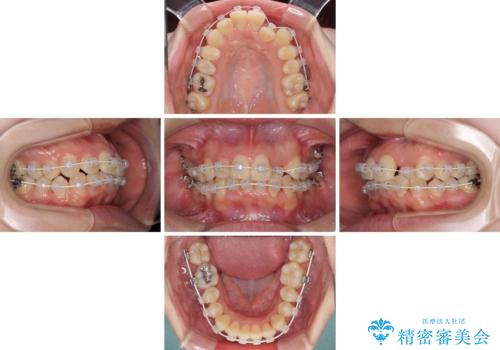

短期間で終了 デコボコをワイヤー矯正で解消

- 上下のデコボコと前歯のクロスバイトを改善したいとのことで来院された患者様です。

極力短期間で治療したいとのことで、ワイヤー装置による矯正治療を行うこととしました。

マウスピースによる矯正治療も提案しましたが、ご自身でのマウスピースの管理の面倒くささと、なるべく早く治療を終えたいとのことで、ワイヤー矯正を選択されました。